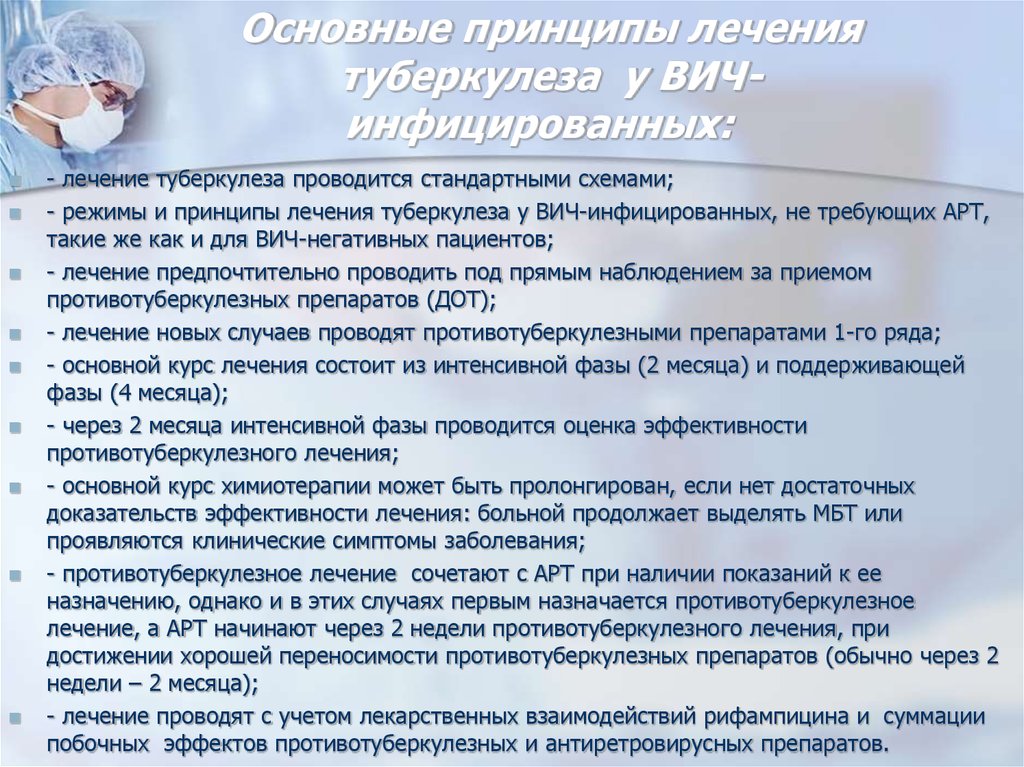

Современные методы лечения туберкулеза